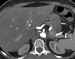

Filmsequenz zu Abbildung 1c: A.mesenterica inferior Die KM-verstärkte MDCT-Angiographie zeigte die kurzstreckige hochgradige Abgangsstenose der A. mes. sup. (Pfeil) und den Verschluss der A. mes. inf. (Pfeilspitze). |